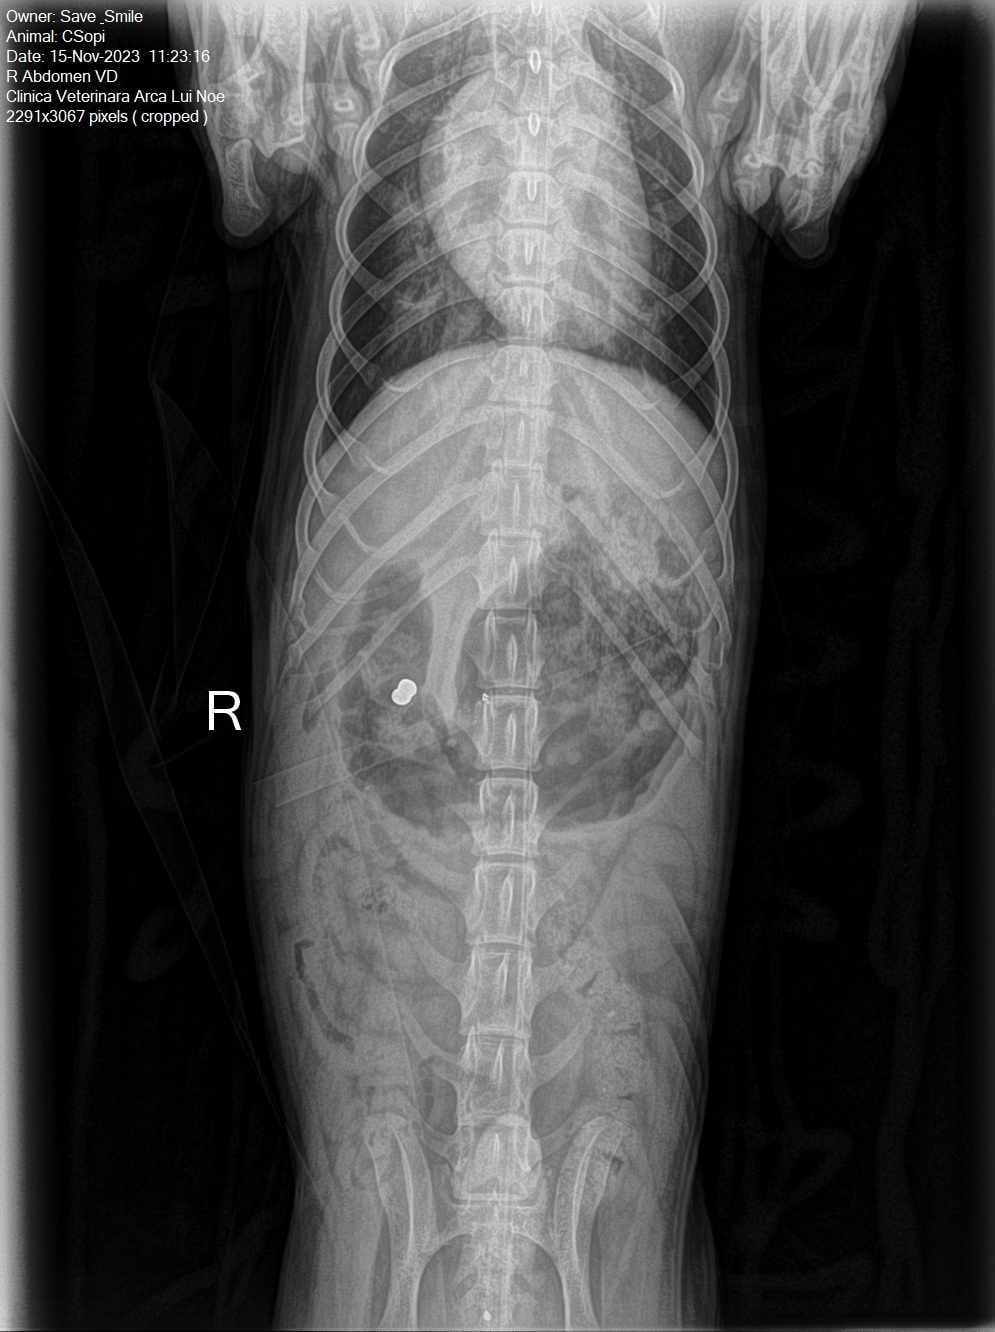

Csopi a été repéré pendant longtemps, rampant dans un champ près d’une ville en Roumanie. Personne ne s’est arrêté pour l’aider… jusqu’à ce qu’il arrive enfin chez sa famille d’accueil. Les radios ont révélé qu’il avait été victime d’un tir dans le ventre. On ne saura jamais qui a pu lui faire ça, ni pourquoi. Ce qui est certain, c’est que Csopi n’a jamais perdu sa gentillesse ni sa confiance envers l’humain.